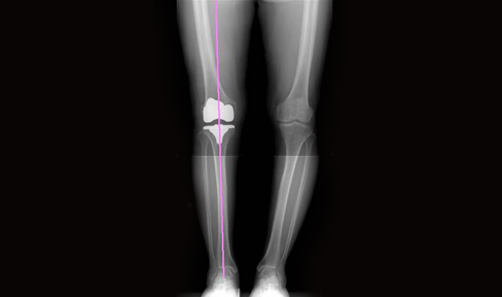

• 인공관절수술 시 뼈의 정렬(MA: Mechanical Axis)이 중요하다는데 이것이 무엇인가요?

뼈의 정렬은 고관절과 슬관절 및 발목의 중심을 잇는 정렬 축이 일직선 상에 정렬된 것을 말합니다.

뼈의 정렬이 잘 이루어지면 체중을 고루 분산시켜 무릎관절이 체중을 지지하는 데 문제가 없습니다.

O다리 X다리의 경우처럼 축이 일직선 상에서 벗어나면 올바른 보행이 어려워 관절질환이 생기기 쉽습니다.

관절질환으로 인해 인공관절수술을 받을 때는 뼈의 정렬을 얼마나 정확히 맞추느냐가 중요합니다.

로봇인공관절수술은 로봇 특유의 정밀함으로 다리뼈의 정확한 정렬이 가능합니다.

정확한 뼈의 정렬은 인공관절 수명을 늘려 재수술률을 낮춰주고 다리의 운동(가동)범위(ROM: Range of motion)도 늘려줄 수 있습니다.